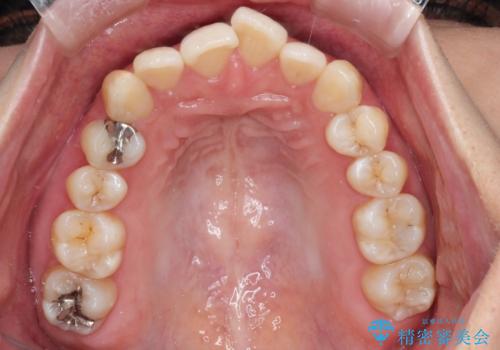

- 前歯のでこぼこが気になると来院されました。

奥歯の噛み合わせは綺麗に噛んでいたため、前歯の叢生(でこぼこ)を、短期間で治療完了するように計画しました。

奥歯の噛み合わせは整っていたため、前歯の並びを美しく修正することに専念できました。マウスピース矯正による治療で短期間で改善しました。